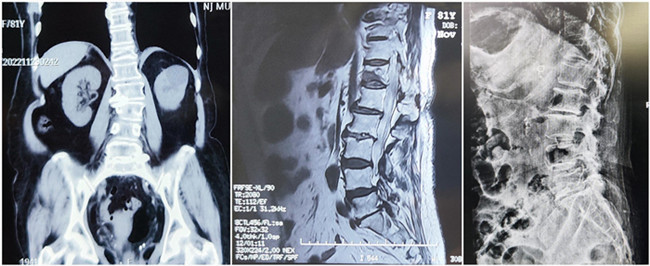

入院诊断:胸椎压缩性骨折(T12)(主诊断);腰椎滑脱;脑梗死;高血压1级;糖尿病。

*患者术前影像

王伯尧主任带领其医疗团队通过与患者的详细沟通与交流,综合评估椎体成形术治疗超高龄椎体压缩性骨折患者的安全性更高,以及病患病情的复杂性,最终决定运用智能化的手段,为患者制定个性化的手术方案,施行骨科机器人辅助下的T12经皮椎体球囊扩张成形术。